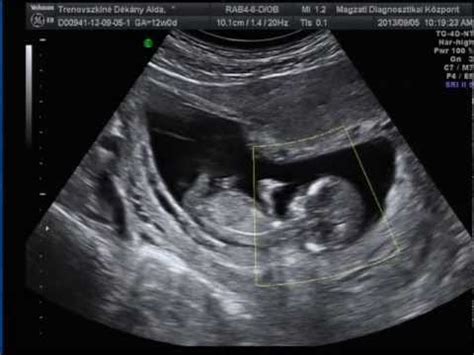

Általában a 12. terhességi héten (de mindenképp a 11. és 13. hét között) történik az első ultrahang-szűrés. Célja a magzat életviszonyainak, a terhesség pontos korának megállapítása, illetve a fejlődési rendellenességek szűrése. Mérik a tarkóredő vastagságot, az orrcsontot, megvizsgálják a magzati gerincet.

A 12. hét nagy vízválasztója az első hivatalos ultrahang vizsgálat, illetve a nyaki redő mérése. A hüvelyi UH során megállapítják a magzat pontos korát. Ez a dátum az utolsó menstruáció első napjától ugyan kiszámítható, de a magzat méretei alapján még pontosabban meghatározható a születés várható ideje, mivel ebben az időszakban az embriók egyformán növekednek. Az UH vizsgálat során nézik a nyaki redőt, amellyel felderíthetőek bizonyos genetikai rendellenességek, első sorban a Down-szindróma jelei. A Down-kóros újszülöttek bőre ugyanis redőkbe emelhető, különösen a tarkótájon. A pozitív szűrőteszt határértéke 2,5 mm. A Down-szindrómára utaló jeleket természetesen más vizsgálatokkal is meg kell erősíteni. Szükség esetén a 12. héten ún. chorion-boholy mintavételre is szükség van, ami segítségével kromoszóma vizsgálatot lehet végezni.

A 12. héten történik a nyaki redő vagy más néven tarkóredő mérés is, ami a Down-kór szűrésének egyik vizsgálata. A nyaki redő vastagszik, ahogy a magzat növekszik, éppen ezért más-más értékek számítanak átlagosnak attól függően, hogy a 11-13. hét között mikor mész ultrahangra. A betöltött 12. héten 3mm-es nyaki redő méretnél szoktak egyéb vizsgálatokat javasolni.

A 12 hetes genetikai ultrahang szűrés érthető módon egyszerre tölthet el várakozással és szorongással is. Alapos betekintést ad méhed belső világába. Ez azért is különleges, hiszen ebben az időszakban nincsenek még közvetlen fizikai élményeid a kisbabáddal kapcsolatban: mozgása még nem érzékelhető és nagy valószínűséggel pocakod sem indult növekedésnek. Az ultrahang képén át találkozni vele - az egyik első “kézzelfogható” élményed lesz gyermekedről.